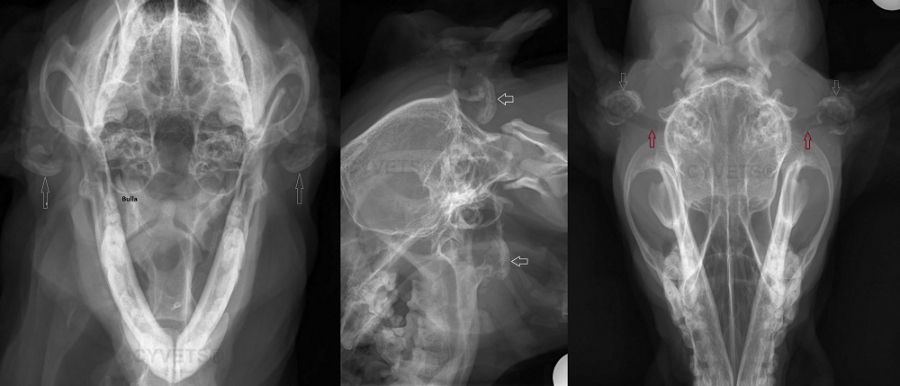

Ear Surgery

Vertical ear canal ablation is a procedure that the upper ear canal (vertical) is removed and a new ear opening is created. It can be performed when the entire vertical canal is diseased but the horizontal canal is normal.